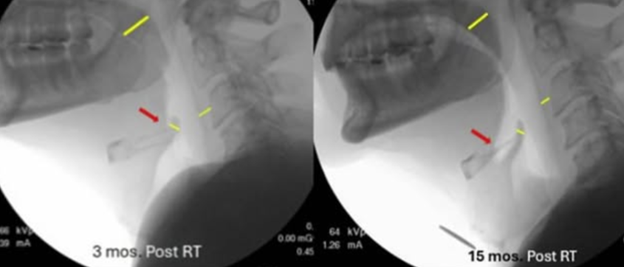

Anatomical Changes

Quick Takeaways

Data collected across interventions.

Example scenarios: head and neck lymphedema, anterior cervical disc fusion.

Steps for Completion

Use the line tool to measure the anatomical site you want to assess prior to, and after intervention.

Example: Use of the line tool in TIMS MVP used to assess improvement in three anatomical sites following lymphatic intervention, and a telestration was added to draw attention to the increased vallecular space (Gregor, 2025).